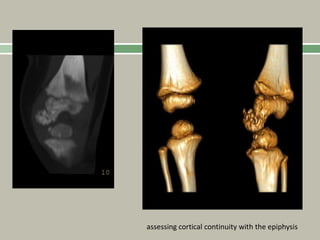

Dysplasia Epiphysealis Hemimelica

(Trevor's Disease)

assessing cortical continuity with the epiphysis